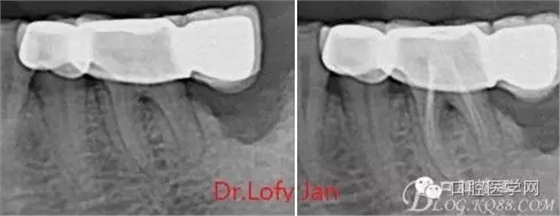

①有助于發(fā)現(xiàn)牙體和根尖周組織的異常改變,如牙折、牙內(nèi)吸收、髓腔鈣化及根尖囊腫;

⑤評價根管充填的質(zhì)量以及療效。

《數(shù)字化根尖片、曲面斷層片、CBCT測量牙齒長度準確性的比較研究》文中顯示:平行投照數(shù)字化根尖片影像長度和牙齒實際長度之間無顯著性差異(P0.05);數(shù)字化曲面斷層片影像長度和牙齒實際長度之間有顯著性差異(P0.05),平均失真率為17.05%。CBCT冠狀面測量結(jié)果中除上頜前磨牙區(qū)、下頜前磨牙區(qū)與真實長度差異無統(tǒng)計學意義(P0.05)外,其余6個分區(qū)差異均有統(tǒng)計學意義(P0.05);矢狀面測量結(jié)果中上頜磨牙區(qū)、下頜磨牙區(qū)、下頜前磨牙區(qū)、下頜尖牙區(qū)、下頜前牙區(qū)與真實長度比較差異均有統(tǒng)計學意義(P0.05)。結(jié)論平行投照數(shù)字化根尖片較曲面斷層片和CBCT能更加精確地反映牙齒的真實長度。

病例分析:曲面斷層片在x線輔助診斷與檢查中目前大多數(shù)文獻和著作都建議只能作為初診拍片檢查手段,不能作為終末疾病的確診與手術(shù)療效的評價指標,臨床大部分中小型門診都因為設備不齊全導致信息偏差很大。